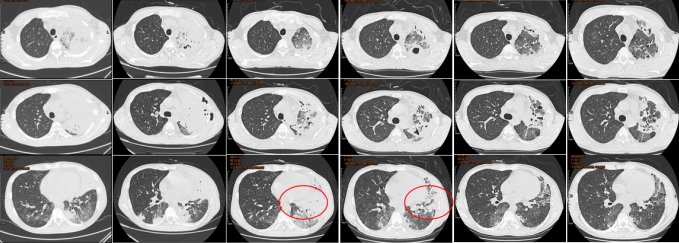

患者在伏立康唑及卡泊芬净联合治疗的情况下,仍然出现影像学进展,考虑治疗效果不佳。从病原学相关因素、宿主相关因素、药物相关因素等三方面进一步明确治疗效果不佳原因。

首先进一步明确病原学,排除其他感染可能,于2021年10月15日予行肺穿刺。

与9月23日相比,11月16日气管镜下见左肺支气管完全通畅,残留少许黏膜粗糙(图15)。

完善嗜肺军团菌尿抗原检测阴性。调整治疗方案,给予左氧氟沙星、哌拉西林他唑巴坦治疗,给予SMZ覆盖肺孢子菌,伏立康唑改为两性霉素B脂质体,同时辅以丙球和粒细胞集落刺激因子治疗(图16)。

改为两性霉素B脂质体后,患者肌酐和尿素氮逐渐升高,后续调整为艾沙康唑治疗,脏器功能有所恢复(图17)。监测艾沙康唑血药浓度均在有效水平。